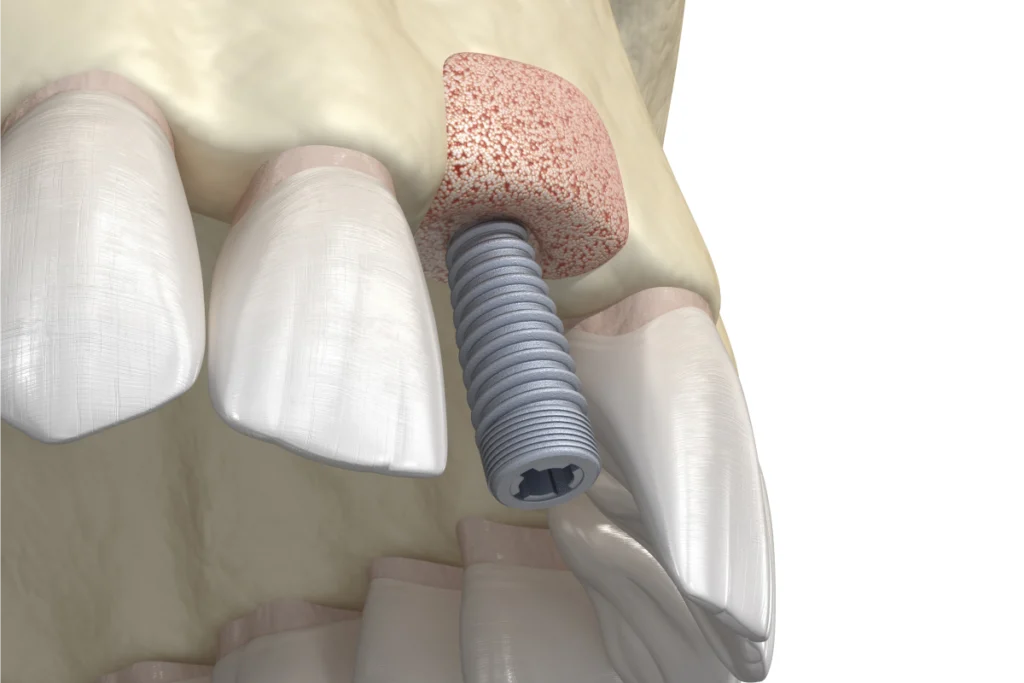

Implantologie • Parodontologie • Esthétique